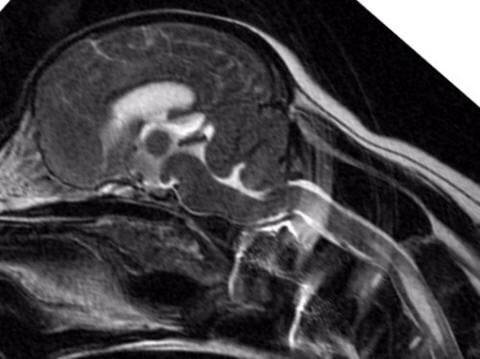

6 years old

No symptoms of SM

Mild malformation, just slightly

compressed cerebellum

Medulla kinked/squashed

No syrinxes present

1.5 years old

Mild to Moderate Malformation, cerebellum

moderately squashed

Herniation of cerebellum

Medulla squashed/kinked

No syrinxes